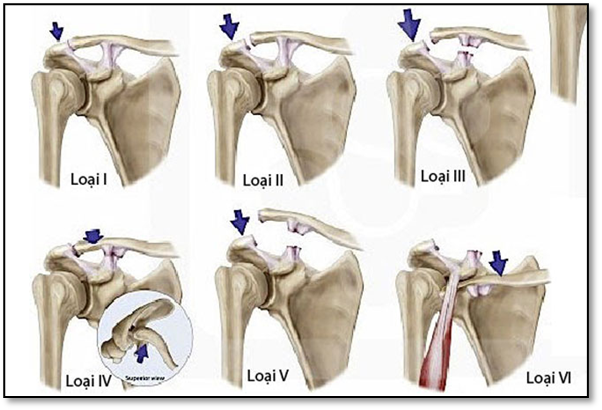

4. Phân độ tổn thương

Tùy theo độ lệch và tổn thương dây chằng, sai khớp cùng đòn được phân thành 6 cấp độ (theo tác giả Rockwood):

• Độ I: giãn dây chằng cùng đòn

• Độ II: đứt dây chằng cùng đòn, giãn dây chằng quạ đòn

• Độ III: đứt dây chằng quạ đòn, khớp cùng đòn trật hoàn toàn

• Độ IV: đầu ngoài xương đòn trật ra sau, vào hoặc xuyên qua cơ thang

• Độ V:  đầu ngoài xương đòn di lệch lên trên rất nhiều

• Độ VI: với phần xương đòn đi lệch xuống dưới mỏm cùng vai hoặc mỏm quạ. Khoảng gian quạ – đòn thu hẹp so với bên lành.

Hình ảnh: Phân loại trật khớp cùng đòn theo Rockwood